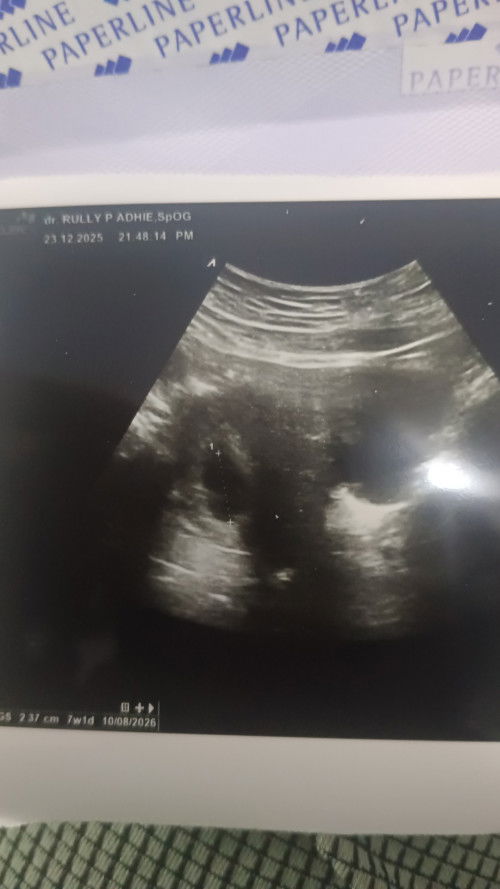

Saya kmrin USG, kalau sesuai HPHT seharusnya 9 minggu. Tapi hasil usg 7 minggu dan sudah ada yolk Salk tapi janin belum terlihat. Disuruh usg 2 minggu lagi, sdh diresep microgest 200 mg tpi masih flek (sdh 2 kali minum - minum nya 2 kali sehari karena flek coklat). Apakah ada bunda bunda seperti saya akhirnya pas usg ada janin berkembang dengan baik, saya dari kmrin sdh nangis bunda. Kuatir, meskipun ini anak ke 4, setelah keguguran 2 kali, anak ketiga 21 bulan. Tapi masih worry #mohonbantujawabbunda #Sharingdong_Bund #bantujawab #sharing #askmommies #sharing

Saya kmrin USG, kalau sesuai HPHT seharusnya 9 minggu. Tapi hasil usg 7 minggu dan sudah ada yolk Salk tapi janin belum terlihat. Disuruh usg 2 minggu lagi, sdh diresep microgest 200 mg tpi masih flek (sdh 2 kali minum - minum nya 2 kali sehari karena flek coklat). Apakah ada bunda bunda seperti saya akhirnya pas usg ada janin berkembang dengan baik 😢 saya dari kmrin sdh nangis bunda. Kuatir, meskipun ini anak ke 4, setelah keguguran 2 kali, anak ketiga 21 bulan. Tapi masih worry #mohonbantujawabbunda #Sharingdong_Bund #bantujawab #sharing #askmommies #sharing